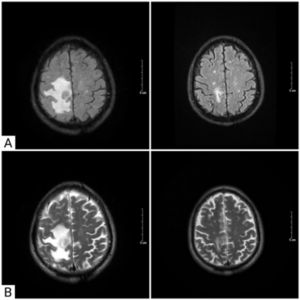

Điều trị bệnh nhân ung thư phổi di căn não giai đoạn muộn tại Trung tâm Y học hạt nhân và Ung bướu-Bệnh viện Bạch Mai

CASE LÂM SÀNG Điều trị bệnh nhân ung thư phổi di căn não giai đoạn muộn tại Trung tâm Y học hạt nhân và Ung bướu-Bệnh viện Bạch Mai PGS.TS. Phạm Cẩm Phương1,2, GS.TS. Mai Trọng Khoa1,2, Sinh viên Nguyễn Thị Hải Anh,2 1Trung tâm Y học hạt nhân và...